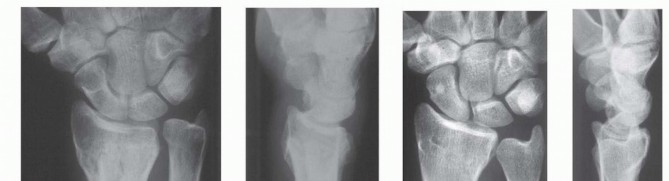

** Intra-articular Distal Radius Osteotomy **Intra-articular osteotomy should be attempted only when there is a simple fracture line that can be clearly identified by direct visualization as well as under image intensification ( TECH FIG 6A-C). Incompletely healed fractures (fewer than 3 to 4 months since injury) are ideal. Depending on the locations of the malunited articular fragments, perform either a dorsal or a volar exposure in the manner detailed earlier. When a dorsal exposure is used, a transverse capsulotomy allows access to the joint and monitoring of the articular osteotomy and realignment. In the case of a volar exposure, the capsule is not incised, but articular exposure may be possible through the osteotomy site. The osteotomy should recreate the original fracture line. This is monitored directly and under image intensification. Reduction is accomplished by soft tissue release and direct fragment manipulation. For many malunions, it is necessary to remove bone or callus from the fracture site to realign the fracture fragment. Callus or bone is removed until the fracture fragment fits properly ( TECH FIG 6D). Provisional Kirschner wires are used to hold the reduction ( TECH FIG 6E,F). The implants are then applied. Dorsally, a single T- or Pi-shaped plate or two 2.0- or 2.4-mm plates (one applied dorsally, ulnar to the tubercle of Lister, and the other applied radially between the first and second dorsal compartments) can be used ( TECH FIG 6G,H). Volarly, a T-shaped plate is usually used. After final plate fixation, provisional fixation is removed. This entire process is monitored using image intensification to confirm appropriate osteotomy site, correction of alignment, and implant placement. Deflate the tourniquet, close the wound, and apply the splint in the manner detailed earlier. 150

### TECH FIG 6 • A-C. PA and lateral radiographs and CT of an intra-articular dorsally angulated malunion. D. A Freer elevator is used under fluoroscopy to reposition the articular fragment. E,F. Intraoperative fluoroscopic views showing provisional correction and fixation. G,H. Final plate and screw fixation. (Copyright Diego Fernandez, MD, PhD.)